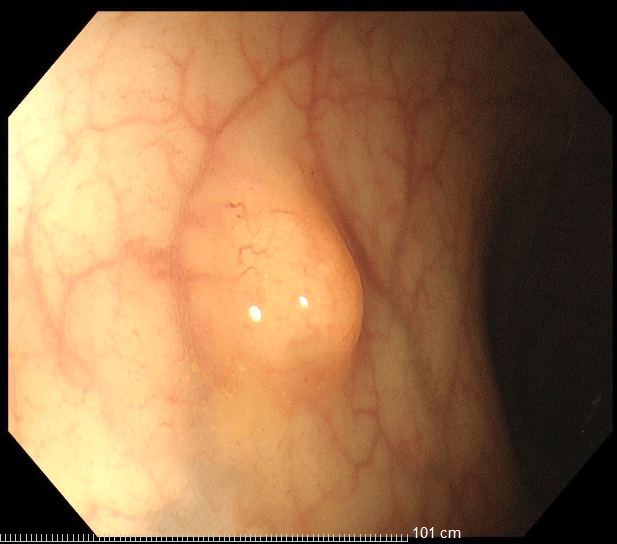

發現早期腸道腫瘤,胃腸鏡檢查很有必要

36歲的王先生在蘇州高新區人民醫院行胃腸鏡檢查時,發現直腸裡有1個息肉和2個黏膜下半球型隆起,表面光滑、顏色發黃,大小直徑約1.0cm,當時便做了超聲內鏡檢查,顯示2個隆起的腫物位於直腸黏膜下層,可能是神經內分泌腫瘤,1個粘膜層隆起的息肉可能是腺瘤腫瘤。消化科團隊立即為王先生進行了腸鏡下黏膜剝離術切